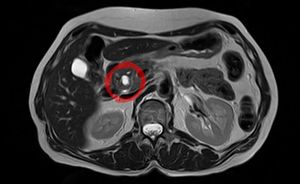

ورم مخاطي حليمي داخل قناة الپنكرياس يظهر في تصوير بالرنين المغناطيسي. | |

ورم مخاطي حليمي داخل قناة الپنكرياس (Intraductal papillary mucinous neoplasm؛ IPMN) هو نوع من الأورام التي يمكن أن تحدث داخل خلايا قناة الپنكرياس. تُنتج هذه النوعية من الأورام مخاطاً،[1] وهذا المخاط يمكن أن يشكـِّل كيسات پنكرياسية.[2] وبالرغم من أن الأورام المخاطية الحليمية داخل قناة البنكرياس هي أورام حميدة، فيمكنهم أن يتطوروا إلى سرطان الپنكرياس.[1] ولذلك يُنظر إلى IPMN على أنها ورم محتمل الخباثة.[3] وبمجرد أن يـُعثر على ورم مخاطي حليمي داخل قناة البنكرياس، فإن خيارات الإدارة تتضمن المراقبة اللصيقة والجراحة الوقائية.[بحاجة للاستشهاد الطبي]